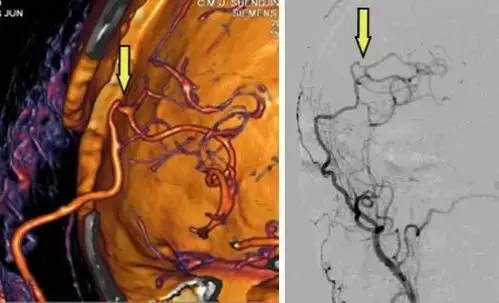

一毫米血管缝14针 - 脑血管搭桥 重建生命通道_患者_手术_治疗

缺血性脑血管病颅内外血管搭桥手术病例分享

慢性脑血管闭塞血管搭桥病例分享

记一例烟雾病患儿脑血管搭桥手术的麻醉